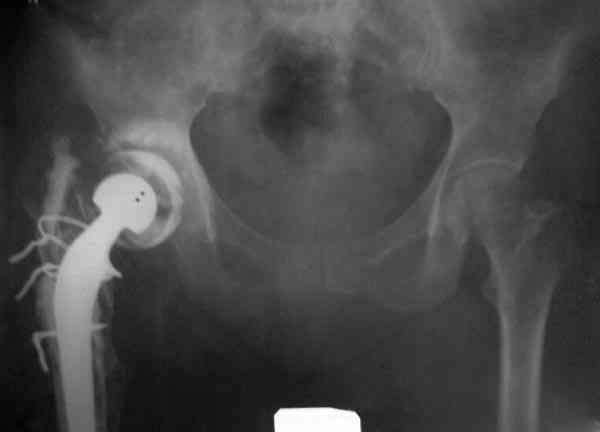

Приглашенный хирург установил ревизионный вариант бедренного компонента без замены ацетабулярного компонента, что осложнилось нагноением и свищами на уровне сустава и средней трети бедра. После двухгодичного безуспешного лечения перевязками и антибиотиками больная обратилась к нам на консультацию.

Повторная операция по удалению тотального протеза с irrigation&debridment, канал после очистки цемента обильно промыт и рассверлен римером.

Для спейсера в бедро использовал старый длинный бедренний компонент меньшего диаметра, облепленный со всех сторон цементом с антибиотиком.

№3-6 снимки с осложнением

и последние снимки.